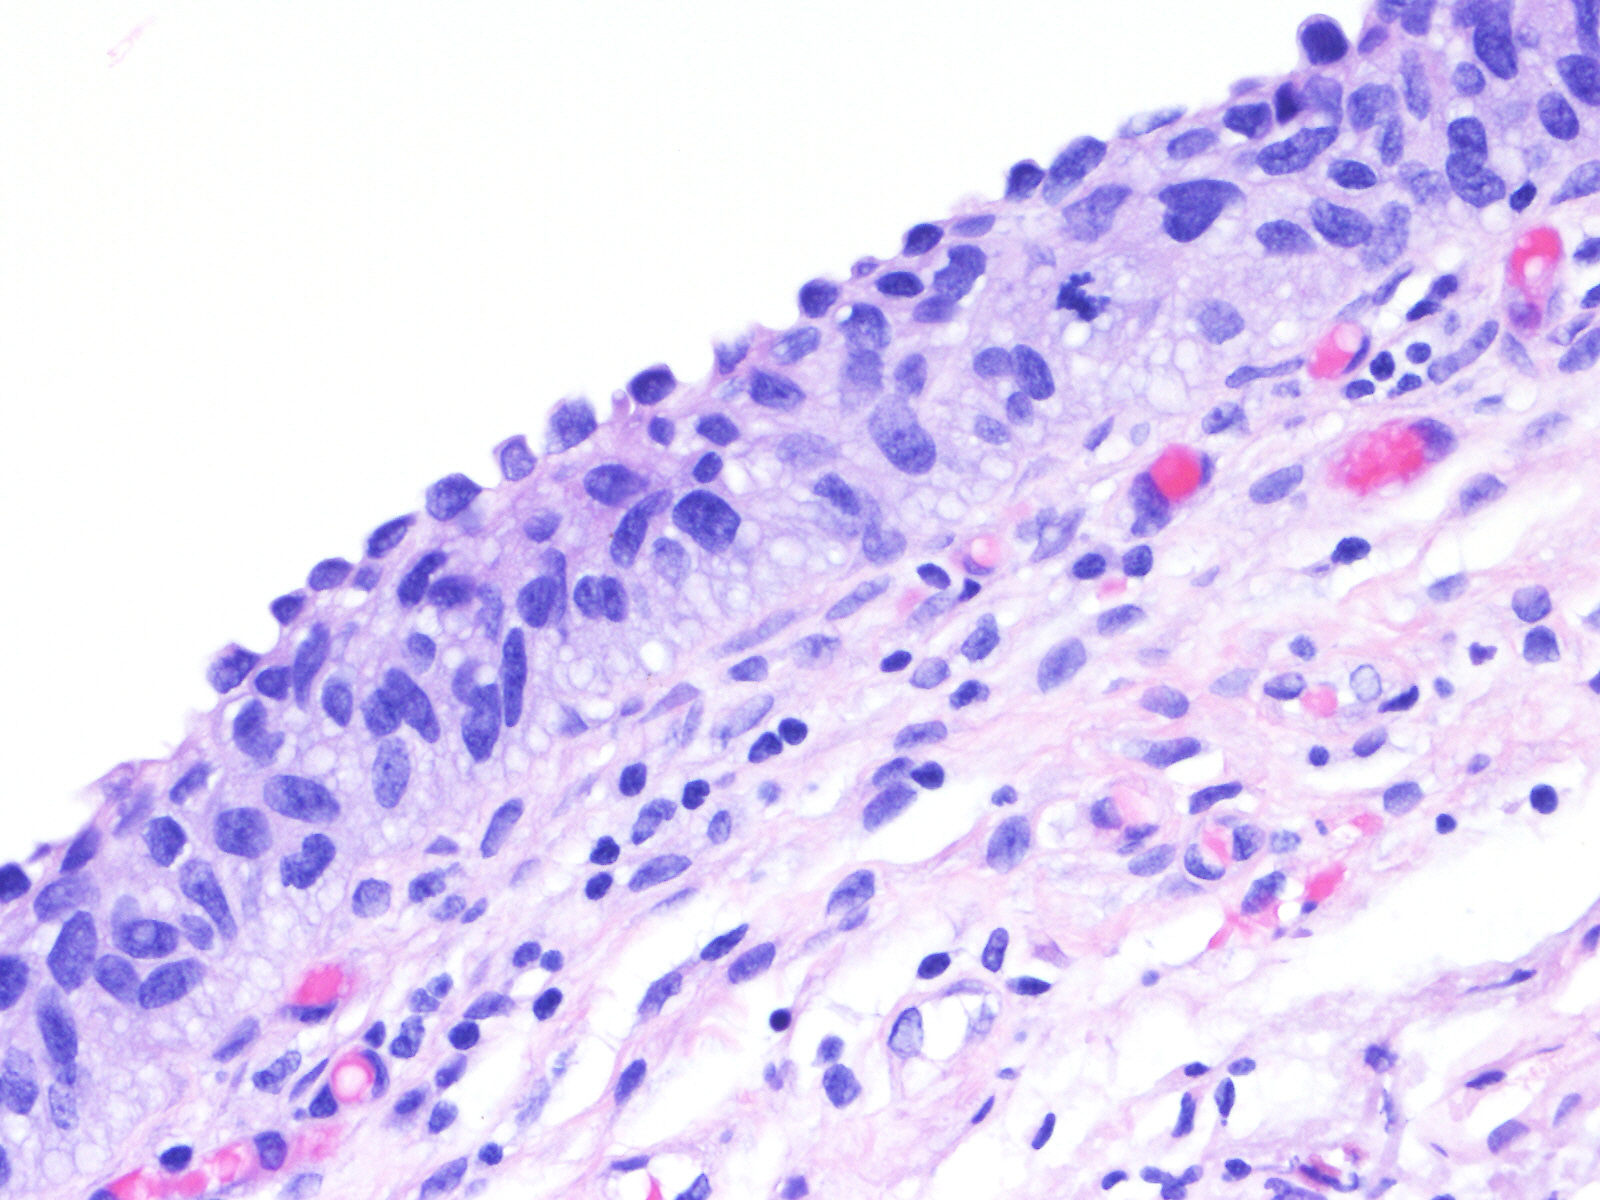

Consensus grade: Carcinoma in situ (CIS)

A 60-year-old female underwent a bladder cystoscopy and biopsy of a 2-cm erythematous lesion at the right posterior bladder wall. About 5 years ago, she was diagnosed with pT1 bladder urothelial carcinoma treated with intravesical therapy.